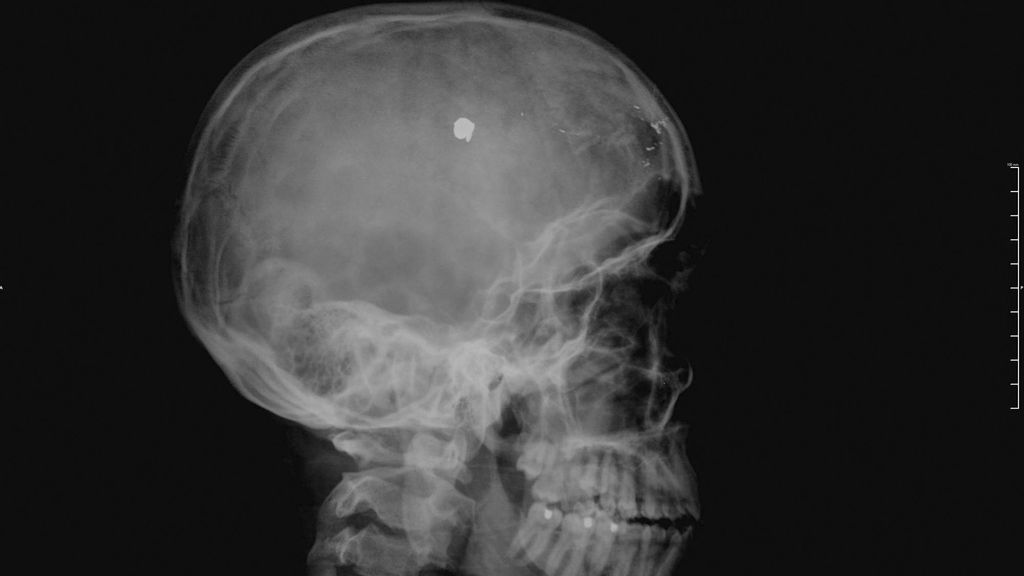

Features & Profiles Tough Nut: Nurse With A Mugger’s Bullet In His Brain For 10 Years Sebastian Bravo, who was 17 when he was shot, has successfully moved forward and chosen to help others. The post Tough Nut: Nurse June 12, 2021 No Comments